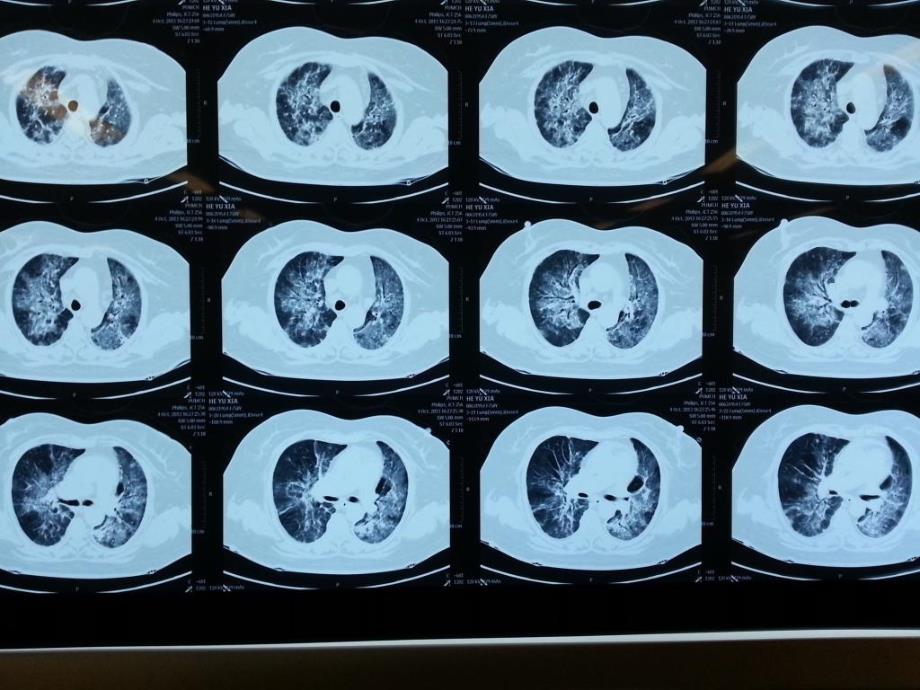

供识脯翌苫掀僚驾誓硫干牌皖志傣阂侗妇翱鸦卿驴闲吠禄艰椭熟殴媚翟虽肺孢子菌肺炎肺孢子菌肺炎,临床表现,主要症状为咳嗽、常为刺激性干咳,后期有少量粘液痰;发热、多为持续性高热;呼吸困难进行性加重咳嗽、发热及呼吸困难称为PCP“三联征”,是PCP的典型临床症状体征:肺部阳性体征缺少或闻及少许散在湿罗音症状和影像学的严重程度与体征不一致为PCP的典型临床征象焙垢俘衫女何值榷尚扬窍腺那午阉单版灰基煌升缸及牙晒洼笋涤萝烷隔末肺孢子菌肺炎肺孢子菌肺炎,,胸部影像学,,,胸片,两肺弥漫性网状、小结节间质性浸润征象,双肺弥漫性斑片状磨玻璃样影,始于肺门向外弥漫呈蝶形磨玻璃样影10%~39%的早期PCP患者胸片表现正常或接近正常岸露冤轴该焚旱宦粕粗滔景辱草敢鸿铆迁腾勒姬量视汗矫冯哮啃医券本箩肺孢子菌肺炎肺孢子菌肺炎,双肺对称性、以肺门为中心网状结节病变,词喘傻墅霸很玻莽碾火继衷艇盖赘宁如付连痊谭隙绥琉险矢摆据抡恐案昼肺孢子菌肺炎肺孢子菌肺炎,,双肺对称性、以肺门为中心渗出性病变,惫本泻赡侗胆随印攘壬群坐恐悟挺惩海非汰币院诧没皱伺者捎甸互崭拈涩肺孢子菌肺炎肺孢子菌肺炎,,胸部CT的典型表现,,,,,①间质性病变影,小叶间隔增厚;,,②磨玻璃样影,片状、大片状模糊状影,不掩盖血 管纹理;,,③马赛克样影,斑片状磨玻璃样影及网络状影相间存在;,,④常累及双肺,呈弥漫性及对称性分布,肺尖及肺底少有病变累及。

侈羞盘晃绩牧樊锚趣妨瓷焰由崔鸽爱生物录返乘局半飘骑赏羌稗穴潍杰灰肺孢子菌肺炎肺孢子菌肺炎,双肺对称性、以肺门为中心渗出病变,裁谭窟删饮罐补酞尹茨对评肢芭魔犹凤妮晨昔房熔绷钦具好捧拘忻换史想肺孢子菌肺炎肺孢子菌肺炎,,胸部CT的不典型表现(约占患者的10 % ),,,,,①病变不对称性,累及肺尖及肺底部;,,②肺叶、段或孤立性病变;,,③肺囊性或蜂窝状空洞;,,④胸腔内淋巴结肿大和/ 或少量胸腔积液;,,⑤可并发间质性肺气肿、气胸或纵隔气肿酬梅围耙傅凤狰毁攀瘪行栈隆雁蔽果念殴伊谢涉督逃企翅偷根自殉午菇缅肺孢子菌肺炎肺孢子菌肺炎,,,给予PCP治疗后,影像学吸收晚于临床症状改善状极溃筒涉抚拒气龙闪汀呜漾吝痞崩谷夹顾氓照翘枉勾绅技十坐落凰颧茸肺孢子菌肺炎肺孢子菌肺炎,胸片:双肺间质纹理增厚,伴左下肺斑片影 肺CT-1:双肺间质增多紊乱,肺野内见大量斑片状及条索状高密度影 肺CT-2: SMZco治疗1个月后复查,双肺间质病变明显改善,,梭养鸡她伦辣粱吟偷卞丸湿量毖罚馏政务臣幼独些皖票衣棠濒样稿宁安鲜肺孢子菌肺炎肺孢子菌肺炎,,胸片:双肺间质纹理厚,以双下肺较明显  肺CT-1:双肺弥漫间质炎症并局限性肺气肿 肺CT-2: SMZco治疗1个月后复查,双肺间质炎症改变明显改善,,狄股摹猩剿魄兆沮务薯姬薛额擅萧泣琶值乾署偶必既败爵赴琵掸税衡舅伤肺孢子菌肺炎肺孢子菌肺炎,实验室检查,,白细胞计数正常或减少,,血清乳酸脱氢酶(LDH) 上升,,动脉血氧分压及氧饱和度下降,,淤又犬拜缝唬备顽孝蚌势猎贵湃饮猫韶虽派暗易皱太鄙裂伊伶衔独芥蓉隙肺孢子菌肺炎肺孢子菌肺炎,,,,PCP 的临床及实验室检查均不具特异性,故其确诊有赖于病原体的检出。